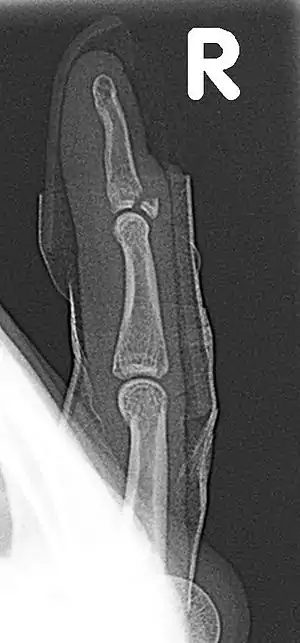

| Fracture of the dorsal base of the distal phalanx by extensor tendon avulsion (Busch fracture) | |

Busch fracture, also known as baseball finger, is a type of fracture of the base of the distal phalanx of the finger, due to being pull on by the extensor tendon.[1][2] Without treatment, a hammer finger may result.

It is common in motorcycle riders and soccer joggers, caused by hyperflexion when the tendon is exercising its maximum tension (the closed hand tightening the clutch lever or the brake lever).[3][4] The underlying mechanism is an avulsion fracture of the distal phalanx by the attached tendon.[5][6][7] It corresponds to the group B of the Albertoni classification.[8]

Avulsion of the part of the distal phalanx to which the tendon is attached, a finger fracture

Appearance: the last joint cannot be straightened. See mallet finger